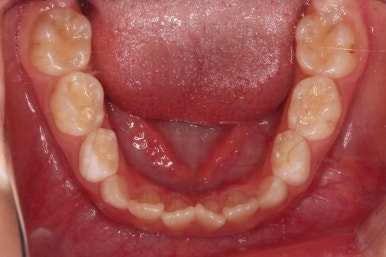

마찬가지로 초진 시 입안의 모습이에요.

아래 앞니가 윗니보다 앞에 있는 "반대교합" 즉, 거꾸로 물려있는 상황이었고요.

어금니 쪽을 보시면(왼쪽 위 사진) 윗니 어금니도 아래 어금니보다 안쪽으로 들어와 있는 "어금니 반대교합"도 있는 상황이었어요.

즉, 윗니가 있는 위턱뼈가 3차원적으로 작은 상황이었던거죠.

이렇게 아랫니들이 윗니보다 앞으로 나와있는 형태의 부정교합을 "앵글씨 3급" 부정교합이라고 합니다.